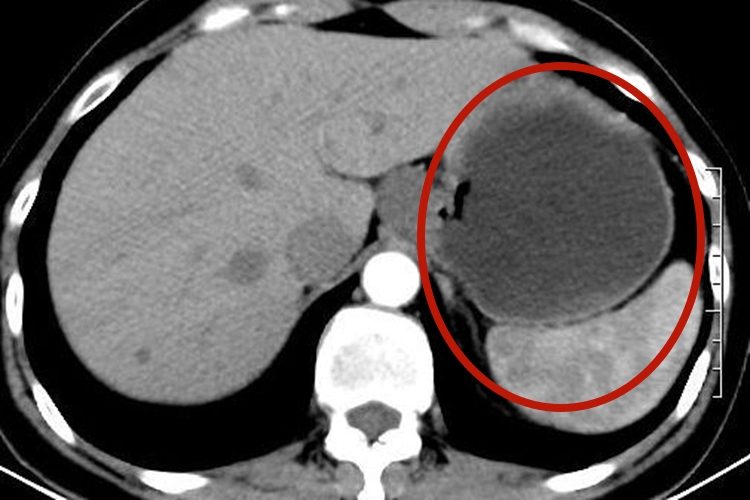

胃囊肿患者可无明显症状,也可出现上腹不适或疼痛。对于发生在贲门部较大的囊肿可引起吞咽困难,发生在幽门处可引起梗阻。胃囊肿患者进行内镜检查可见圆形或柱状隆起肿物,大小不定,表面光滑。